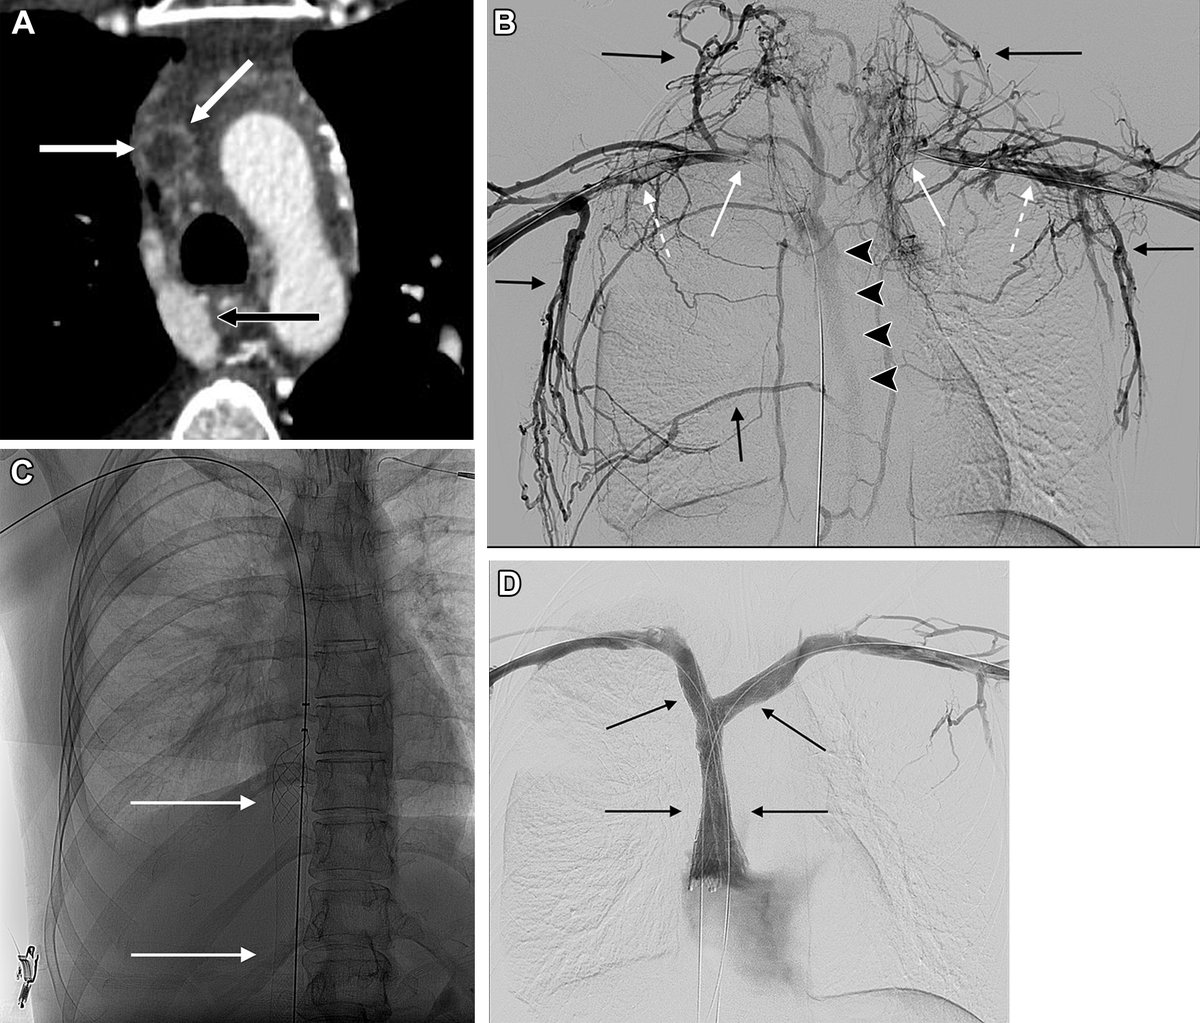

@RadioGraphics

RadioGraphics

4 days

Thoracic central vein obstruction is increasingly device-related. Endovascular recanalization and stent reconstruction enable rapid symptom relief and durable patency when guided by meticulous imaging, planning, and technique. https://t.co/PPhBTAHdUF